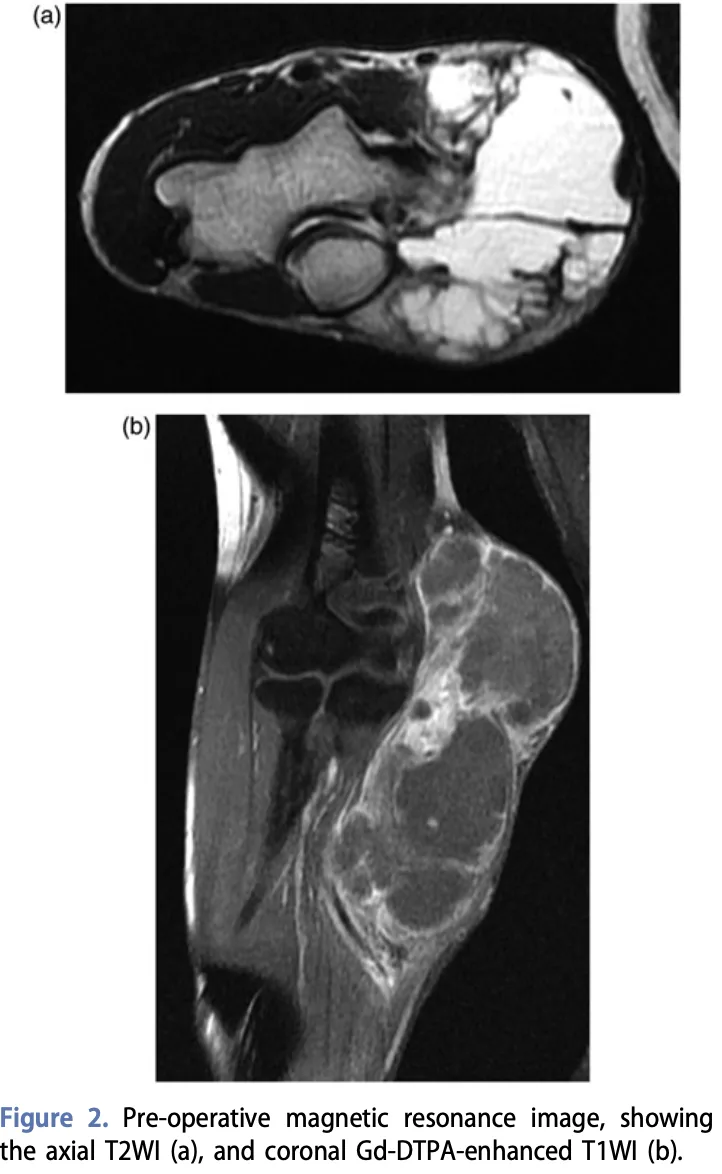

造影MRI(b)では, 腫瘍の内部に造影されない(血行障害で腫瘍が死んでしまった(壊死えし))領域があることが悪性腫瘍の特徴です.

3カ月前から右肘に腫瘤を認め, 1カ月前に先輩医師のクリニックでMRI検査を受け, 軟部腫瘍を指摘された高齢の方でした.

紹介状の日付は4週間前. 腫瘍は, 1カ月の間に4 cm大から5 cm大へと増大していました.

造影MRIでは, 腫瘍内部に血流の乏しい壊死領域が確認されました.

これは悪性軟部腫瘍(軟部肉腫)を強く示唆する所見です.